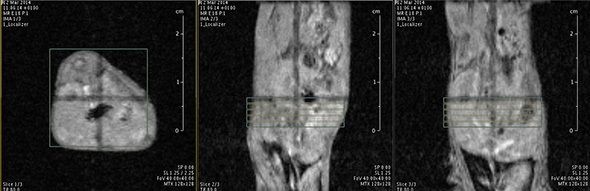

I think that also the low-field, let’s say the low/intermediate field to work at the 1 Tesla for instance as in the case of this beautiful Icon system, this gave us unique possibilities. Anytime we use a gadolinium-based agent or more in general a paramagnetic basic agent the best field is the 1 Tesla.

So, we can show that there is a real advantage of working at 1 Tesla in comparison to for instance 7 or 9 Tesla when one is using a relaxation enhancer to target a specific epitope in the region of interest.

Whereas until the late 90s we were essentially attracted by the development of contrast agents for MRI application and being restricted in some domains, in particular with the vascular and the extra vascular domain, because it is always very difficult to reach enough sensitivity with MRI contrast agents entering into cells.

The possibility to use complementary imaging modality was our task in the last 10 or so years. And this changed quite drastically the structure of our group, because we have to get users quickly used to the basic principles in order to have efficient imaging reporter for the other imaging modalities.